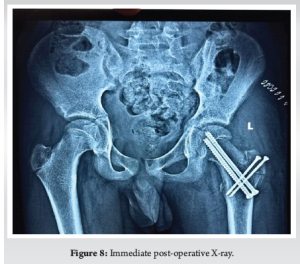

A 15-year-old boy with body mass index (BMI)-18.6 kg/m2 presented to the emergency department with acute left hip pain and inability to bear weight. The pain began after a minor stumble while playing at his school, though he denied any significant trauma. He was initially able to weight bear but gradually pain progressed leading to difficulty in walking and unable to weight bear over the past 24 h. His medical history was unremarkable. His family history was negative for hip disorders, early-onset osteoarthritis, or metabolic conditions. Examination revealed lower limb in flexion, shortened and externally rotated with diffuse tenderness over hip region. Radiography showing widening and irregularity of the left physeal plate, posterior displacement of the femoral epiphysis relative to the femoral neck (Fig. 1] and Klein’s line failed to intersect the epiphysis (positive Trethowan’s sign) (Fig. 2a). Based on clinical presentation and imaging, the patient was diagnosed with: Unstable, severe SCFE (Fig. 2b) (Southwick angle >50°), high risk for osteonecrosis due to inability to bear weight. Given the severity of displacement and instability, MDP was selected over traditional ISP to restore hip anatomy and preserve femoral head vascularity. Patient underwent the MDP through a Ganz surgical hip dislocation approach, performed under general anesthesia. A straight digastric osteotomy of the greater trochanter was performed leaving the most posterior fibers of gluteus medius tendon intact (Fig. 3). This did not potentially endanger the deep branch of the medial femoral circumflex artery. Mobilization of the trochanteric fragment together with the vastus, gluteus minimus, and medius muscles was done ventrally to expose the capsule. A Z-shaped capsulotomy was performed providing access to the displaced epiphysis (Fig. 4). Femoral epiphysis was temporarily pinned with 2 mm Kirschner wires. The viability of femoral epiphysis was ensured by drilling of the femoral head. Dislocation of femoral head was done by flexion and external rotation and placement in a sterile bag by the side of operating table. Full inspection of acetabulum was done to see any corresponding chondral damage. After relocating the head, retinacular soft-tissue flap containing deep branch of medial femoral circumflex artery, the periosteum, the piriformis muscle, part of the posterior capsule, and the short external rotators was developed (Fig. 5). Distally, the flap was mobilized till the level of the lesser trochanter which reduced the tension from the retinacular vessels. Complete epiphyseal mobilization (Fig. 6) and carefully separating the femoral epiphysis from the posteriorly displaced metaphysis was facilitated by external rotation. The excess callus formation of the metaphysis which was seen was resected until a spherical surface of neck became reapparent. The epiphysis was then reduced manually on the metaphyseal stump (Fig. 6). A 3.0 mm Kirschner wire was placed anterograde for temporary reduction and checked under fluoroscopy for capital realignment. Internal fixation was done using one fully (75 mm) and one partially (80 mm) threaded 6.5 mm cannulated cancellous screws for stable fixation (Fig. 7). Retinacular soft-tissue flap was reattached back with tension free sutures. Similarly, capsule was closed without tension. Osteotomy site was fixed at the end with two 3.5 mm cortical screws. In immediate post-operative period (Fig. 8), the patient was kept non-weight-bearing for 6 weeks with strict activity modification, physical therapy initiated with passive range-of-motion (ROM) exercises at post-operative day 2 to prevent stiffness, pain was well controlled with non-steroidal anti-inflammatory drugs, and no early post-operative complications were noted. 6 weeks post-operative, radiographs showed stable fixation with no further slip progression, early signs of physeal healing were observed. Patient regained near full near-full ROM with no significant pain (Fig. 9). Three months post-operative (Fig. 10), the patient transitioned to full weight-bearing. At present, the patient is 4 months post-operative and able to do regular activities without restriction. Radiographs showed complete healing of the osteotomy site No clinical or radiographic evidence of FAI or chondrolysis were found.